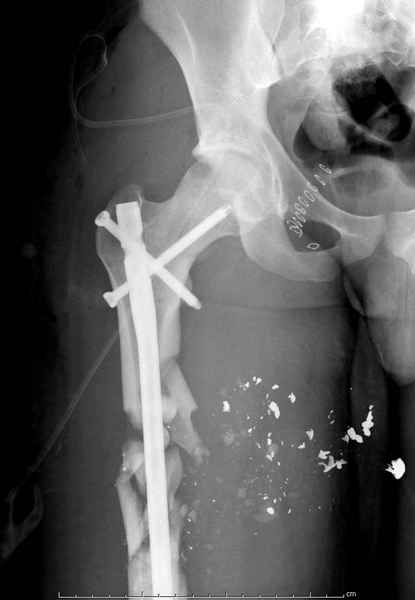

Re: Огнестрельный перелом бедра с дефектом кости.

Здесь несколько примеров из нашей практики:

2 перелом бедра